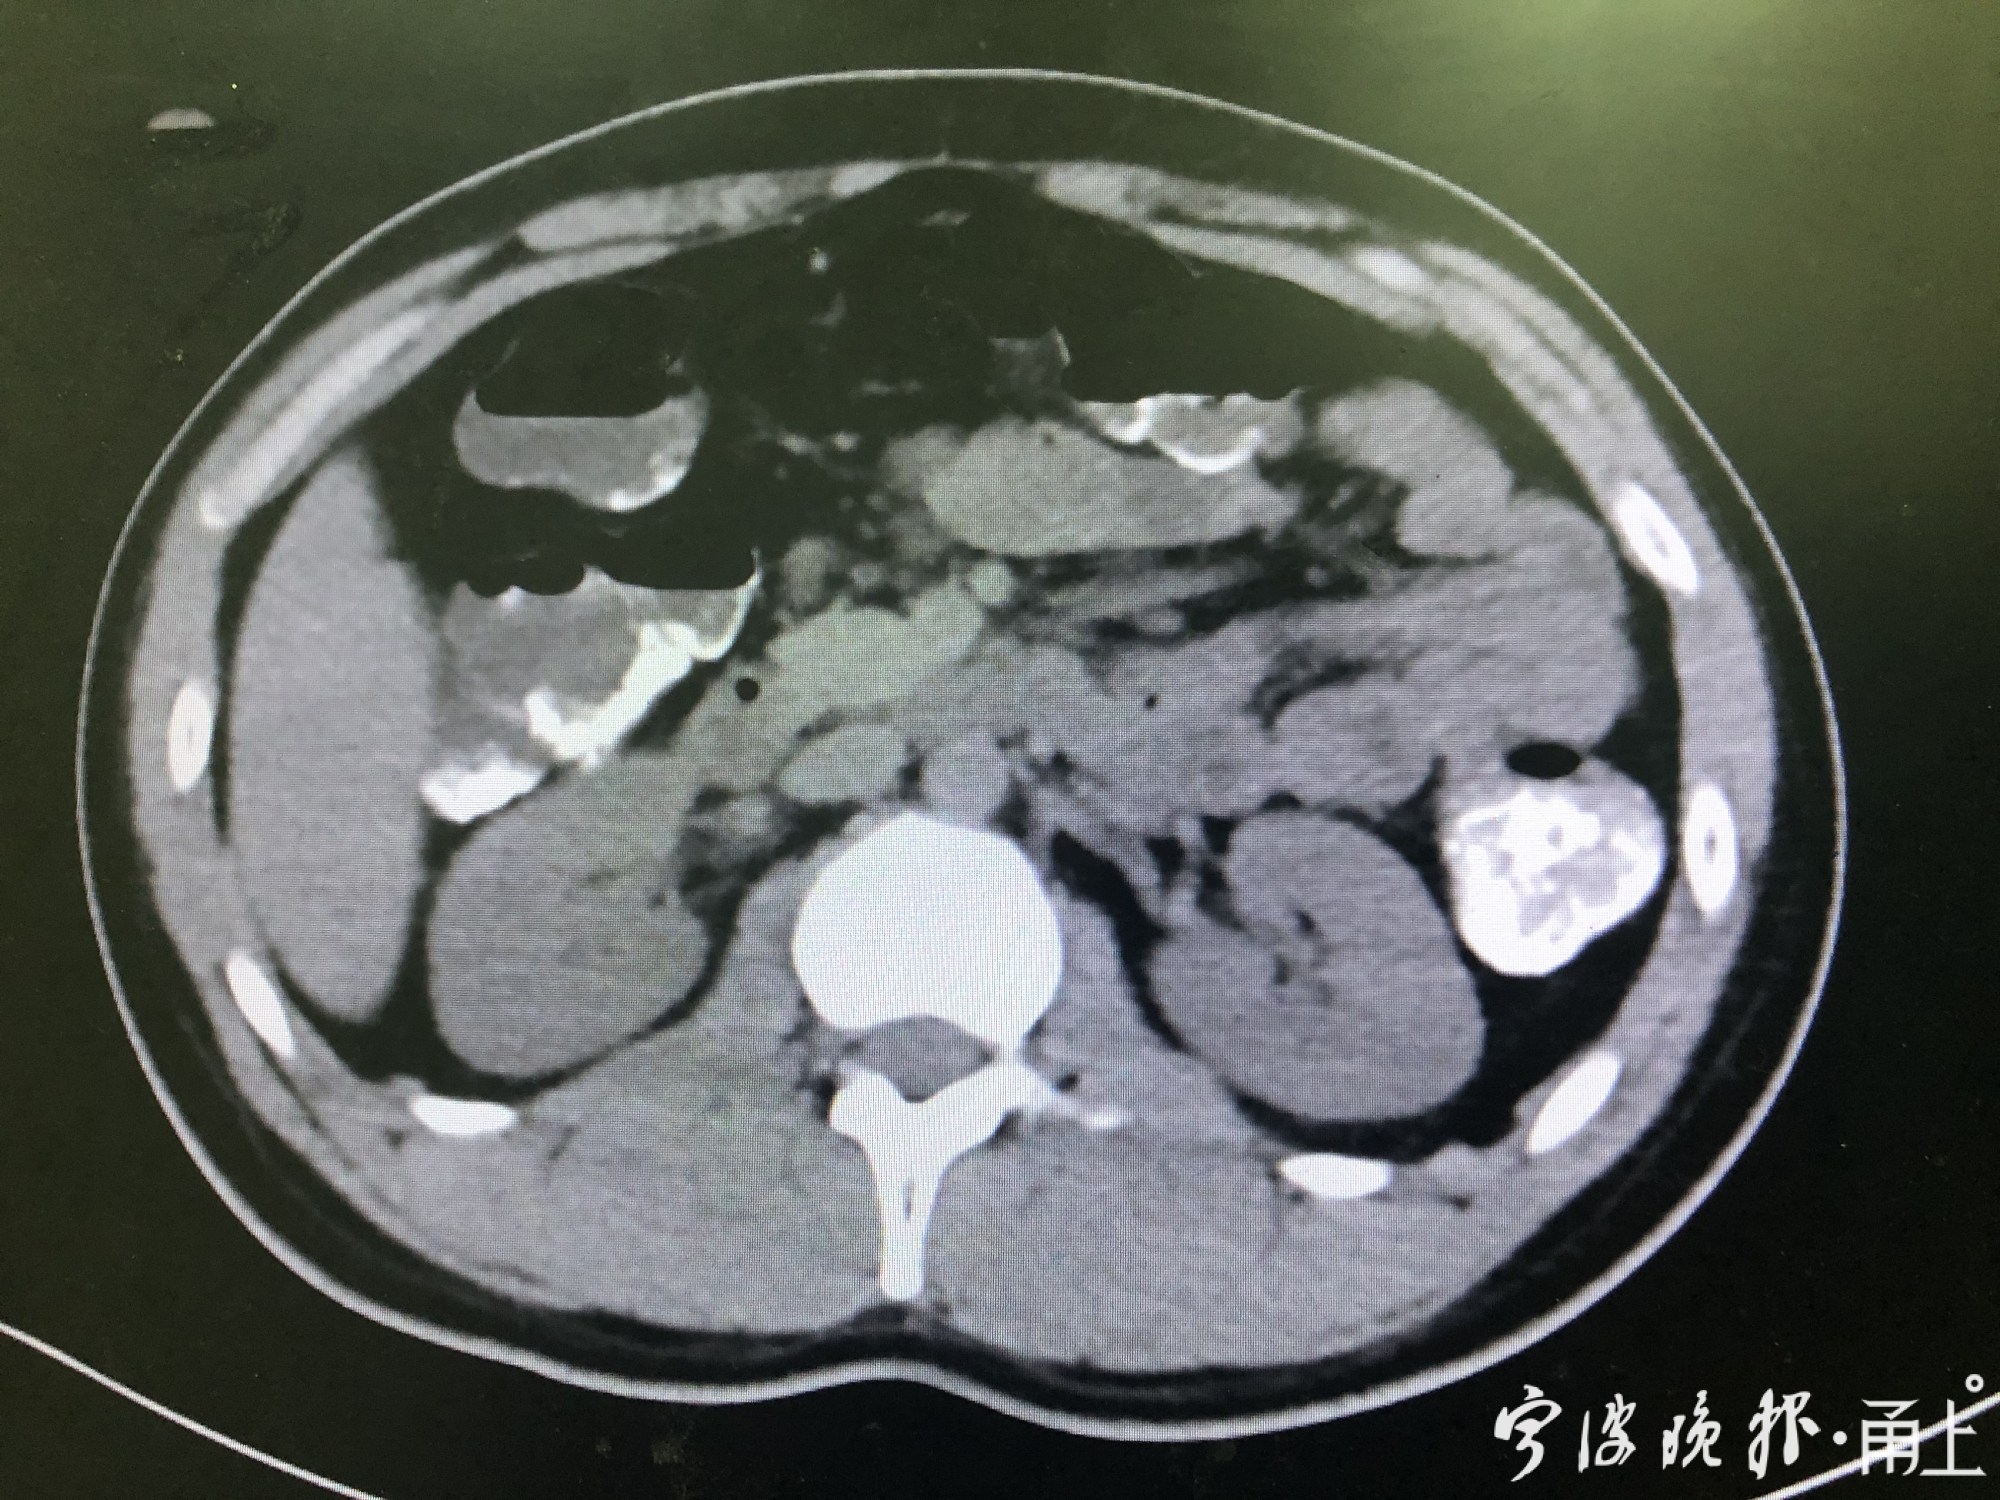

接诊的国科大华美医院急诊科副主任医师乐元洁立刻给小王做了CT检查,发现小王的胃肠道里有些高密度影,提示是重金属。医务人员立刻准备为小王洗胃,通过洗胃机将大量牛奶灌入小王的胃袋,再连同胃内容物一起抽出,清除胃内未被吸收的毒物并清洁胃腔。随后医生们为小王安排了入院观察,并配了特定解毒药,目前小王的身体恢复良好。